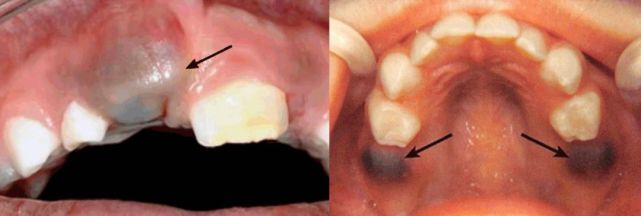

但若治疗不及时,炎症则有可能会毒害到乳牙后方的“小种子”——恒牙胚。

乳牙后方的恒牙胚(发育中)

带着缺陷萌发出来的恒牙,则有可能变成特纳牙,也就是牙釉质发展不全的牙齿。

特纳牙(turner tooth):乳牙根尖炎症侵犯恒牙胚,导致恒牙釉质发育受损

所以说,虽然孩子的乳牙以后会替换,一旦发炎也应及时治疗。